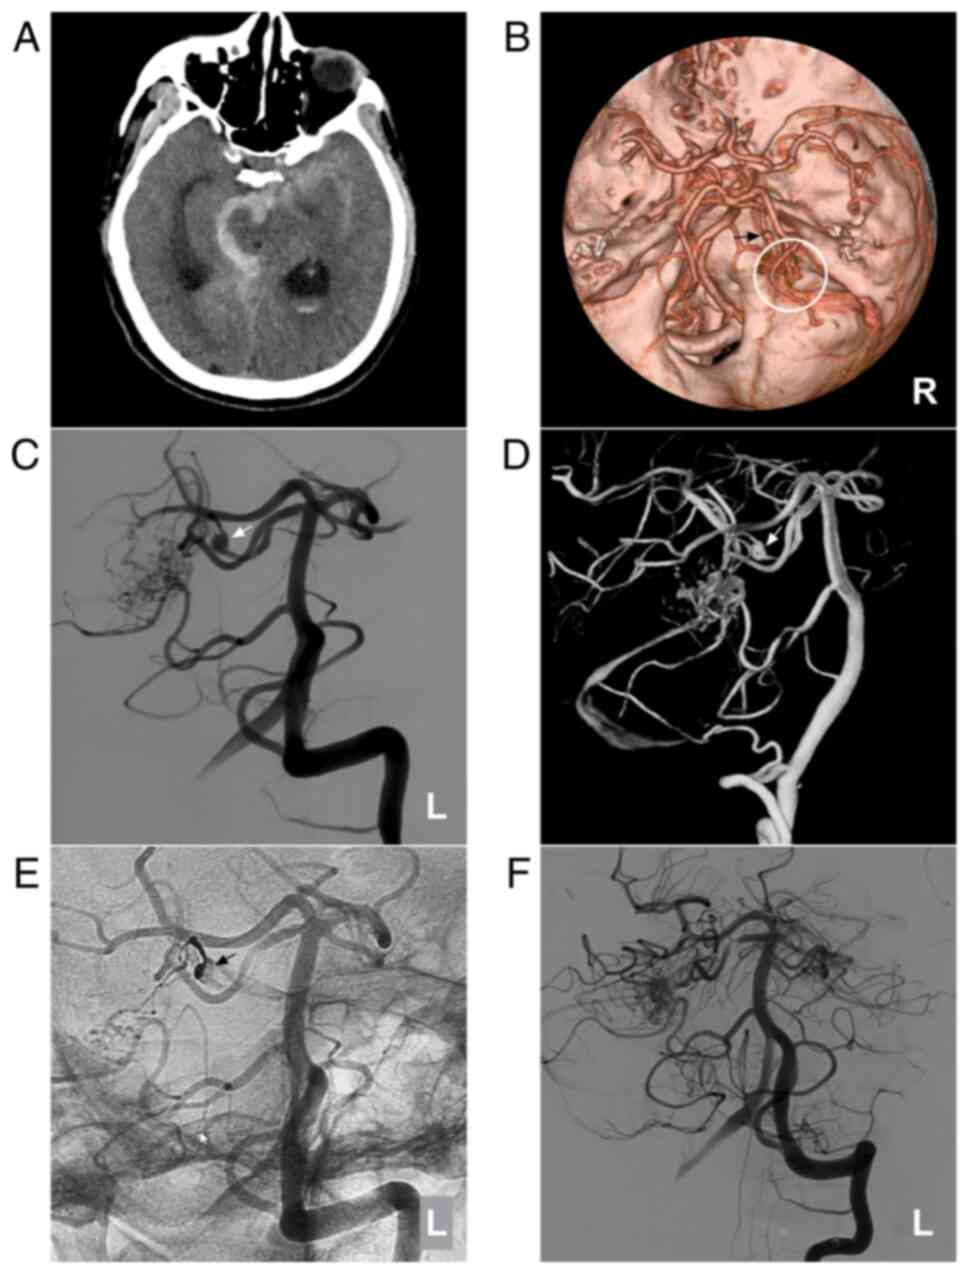

Figure 5

AVM combined with a prenidal aneurysm on the SCA. (A) Brain CT scan showing subarachnoid hemorrhage in the right ambient cistern. (B) Brain CTA showing the right SCA feeding the AVM (circle), and an aneurysm (arrow) is observed. (C) Two-dimensional and (D) three-dimensional DSA showing that the aneurysm (arrow) can be observed. (E) Unsubtracted DSA showing that the prenidal aneurysm was occluded with Onyx™ casting (arrow). (F) Following embolization, the aneurysm was not observed. The case presented in this figure was a 67-year-old male with a sudden headache; he was awake after its onset. Following EVT, conservative treatment was administered, and no EVT complications were observed. His health status is currently classified as normal. AVM, arteriovenous malformation; CT, computed tomography; CTA, computed tomography angiography; DSA, digital subtraction angiography; L, left; R, right; SCA, superior cerebellar artery.